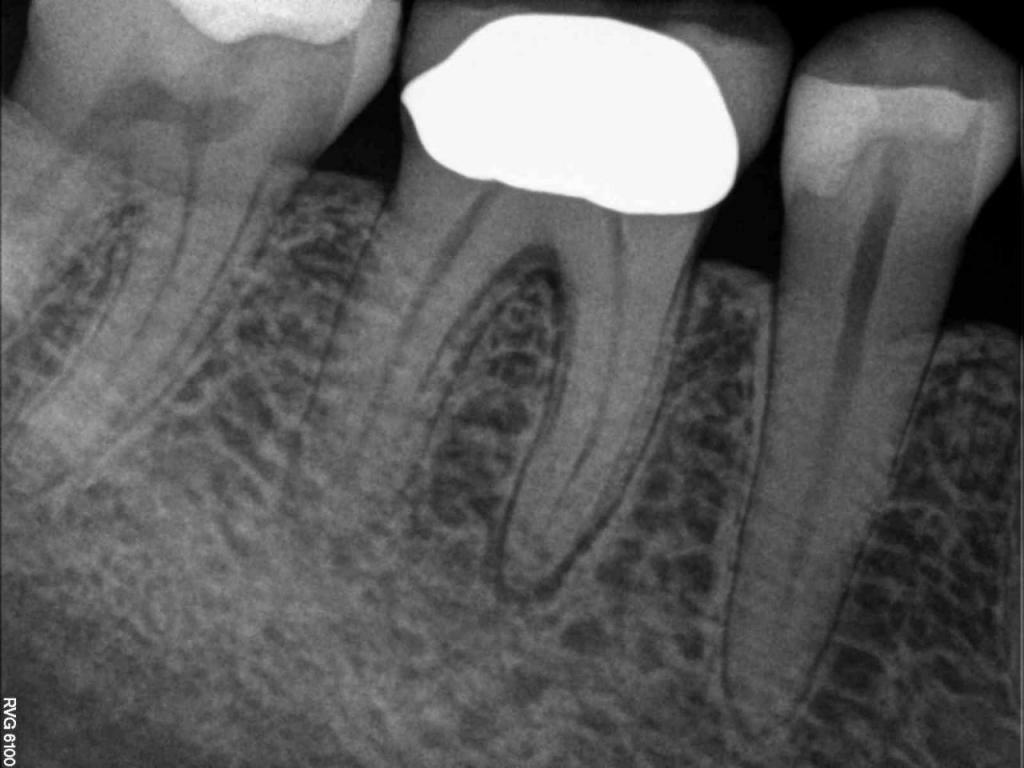

Although the primary use of visual documentation is for patient charts, dental images provide a meaningful way to communicate with patients about their care needs. Digital imagery is a vital tool for educating patients and an essential way to share information with office staff, colleagues and referring doctors. Digital technology has allowed Southcenter Endodontics to enhance our practice and improve the delivery of care to our patients. Below you will see images of “Before” and “After” scenarios. By clicking on a thumbnail image below, you will be able to see and a larger view of the x-ray taken at Southcenter Endodontics and notations made regarding each film.